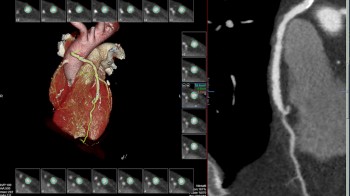

- MSCT koronarografija (prikaz krvnih žila srca CT-om, bez neugodnosti i komplikacija koje nosi klasična koronarografija), u saradnji s Poliklinkom dr.Al-Tawil